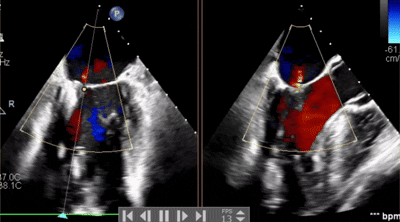

術(shù)中操作

全麻后,在心前區(qū)的肋間切開(kāi)3-4CM小切口,暴露心臟的心間位置,將二尖瓣夾合系統(tǒng)送入左心房,順利到達(dá)病變二尖瓣區(qū)域。在經(jīng)食道超聲輔助下,術(shù)者通過(guò)反復(fù)評(píng)估二尖瓣反流位置、抓捕位置、反流程度,最終在3區(qū)位置垂直于二尖瓣閉合線方向進(jìn)行巧妙?yuàn)A合最終植入1枚ValveClamp®MVC-Ⅱf夾。手術(shù)中導(dǎo)管操作時(shí)間僅30min,共夾合2次。患者術(shù)后反流程度從大量轉(zhuǎn)至微量,手術(shù)取得圓滿成功。

手術(shù)步驟

5.下夾撤入心室后,捕獲夾合瓣葉,第一次夾合位置為3區(qū),夾合后2區(qū)一側(cè)殘余反流量2+,不符合術(shù)前預(yù)期,推開(kāi)上下夾;

6.調(diào)整夾子軸向后再次夾合,夾合后剩余反流量1+,符合術(shù)前預(yù)期,解離上下夾。